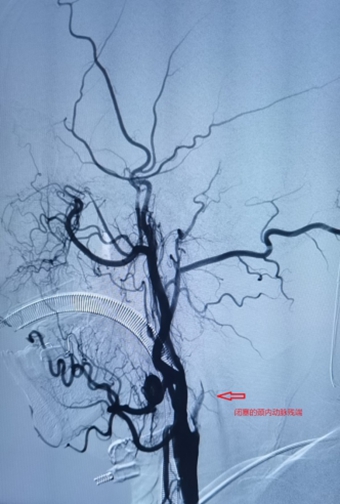

6月7日下午,家住长竹园乡的刘先生突然出现左侧肢体无力,双眼向右侧斜视(凝视),言语不清、口角歪斜等症状,下午3点家属将其送入我院,急诊行头颅CT未见出血,但其右侧颈内动脉末端及大脑中动脉可见高密度征,考虑为大血管病变所致的急性脑梗死,NIHSS评分:14分,mRS评分4分,因无溶栓禁忌,与家属沟通后给予急诊静脉溶栓(阿替普酶,0.9mg/Kg体重)治疗。溶栓大约10分钟左右患者开始出现烦躁,头痛,(NIHSS评分:14分,mRS评分5分)急诊头颅CT未见出血转化,在右侧大脑中动脉供血区出现大片状低密度灶,情况变得更加凶险,卒中团队综合考量认为患者此时急需血管开通治疗以避免脑细胞进一步坏死,再次与患者家属沟通病情后开始急诊取栓治疗。下午3点30分患者被紧急推入介入手术室。

在卒中中心团队的默契配合下,手术顺利取出血栓,实现左侧大脑中动脉完全再通。从动脉穿刺成功到血管完全再通历时仅40分钟。术后患者生命体征平稳,术后1周,患者病情稳定,神志清楚,对话流利,凝视症状缓解,NIHSS评分由14分变为8分。